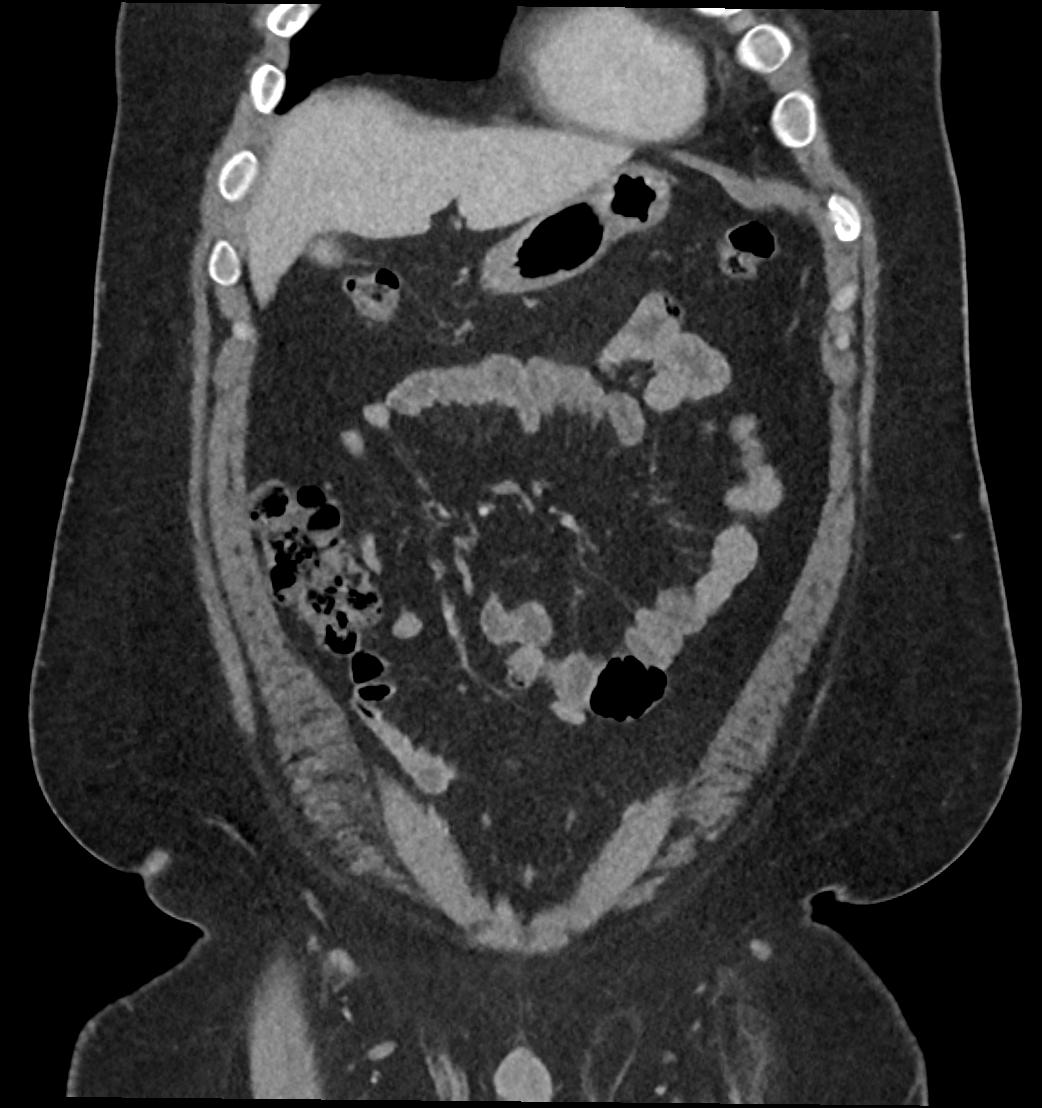

Patient: Padmakumar A. , *1988-04-24, PID: 3000069741773230809

Study Description: CT ABDOMEN

Image Series: Abdomen Cor 3mm [4]

<< Previous | Image 40 of 119 | Next >>